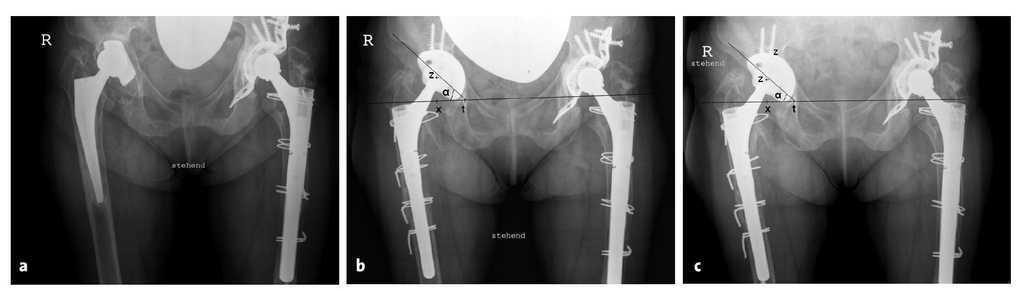

Todos los pacientes se siguieron de forma prospectiva durante el primer año postoperatorio, todos a los 3 meses y a los 6 meses de manera clínica y radiográfica. En el análisis de las radiografías y siguiendo los criterios de Dominikus et al7, se tomaron dos proyecciones digitalizadas de pelvis anteroposterior con las referencias claramente identificables (a las dos semanas postoperatorias y en la última exploración). Aquí se obtuvo una exploración en la radiografía en busca de radiolucencias en las zonas I, II y III según DeLee y Charnley4. Siguiendo las recomendaciones de Cordero-Ampuero et al3, se valoraron las radiolucencias > 2 mm como signos de aflojamiento. Los posibles cambios a nivel acetabular se analizaron según el método de Nunn et al16 (figs. 14a a 14c), con lo cual las mediciones que pueden variar con respecto a la distancia del paciente al chasis y variaciones de la anatomía de la pelvis se corrigieron según las recomendaciones de Nunn et al16. Las alteraciones de ≥ 3 mm en dirección horizontal o vertical2,16 y/o las variaciones del ángulo de inclinación a partir de 5º3,16 se aceptaron como migración definitiva. El promedio de seguimiento fue de 35,8 ± 8,8 meses (26-53 meses).

Figuras 14a a 14c. Exposición del análisis de aflojamiento según Nunn et al16 a propósito de la evolución del caso de una paciente de 78 años con un recambio de prótesis de cadera derecha con un defecto acetabular del tipo Paprosky 2C con un defecto de la ceja posterior. t: figura de la lágrima; x: punto de corte entre la línea que une las dos lágrimas y la perpendicular del centro de la cabeza; z: centro de la cabeza. Las alteraciones del segmento zx explican una migración vertical; las alteraciones del segmento tx se refieren a una migración horizontal, y la variación del ángulo a implica una variación del ángulo de inclinación. a) Visión de la radiografía de pelvis anteroposterior preoperatoria con identificación del cótilo aflojado y del vástago cementado. b) Radiografía anteroposterior de pelvis a las cuatro semanas postoperatorias de un recambio colocando un cótilo AllofitSTM y con un vástago de revisión modular Revitan curvado (Zimmer GmbH, Winterthur, Suiza). c) Radiografía anteroposterior de pelvis a los 30 meses postoperatorios.

La escala de valoración de la cadera de Harris10 aumentó de 46,4 ± 15,5 puntos de forma continua a 87,3 ± 15,0 puntos a los 24 meses postoperatorios (tabla 1). Ninguno de los cótilos mostraron signos radiológicos de aflojamiento; sin embargo, dos cótilos presentaron criterios radiológicos de migración (desplazamiento horizontal o vertical de 3 mm o un cambio de ángulo de al menos 5º2,3,6,16). En un paciente de 75 años con artritis reumatoide y con un defecto óseo del tipo Paprosky 2C se dio a los seis meses postoperatorios un aplanamiento del ángulo de inclinación de 5º, y en un paciente de 56 años con una necrosis de cabeza femoral de base y un defecto de tipo 3A de Paprosky se presentó a los seis meses postoperatorios un aplanamiento del ángulo de inclinación de 6º en combinación con un desplazamiento vertical de unos 3 mm. Ambos pacientes no se quejaron de dolor. En un caso se dio una luxación (un mes de postoperatorio) que se pudo tratar de forma conservadora.